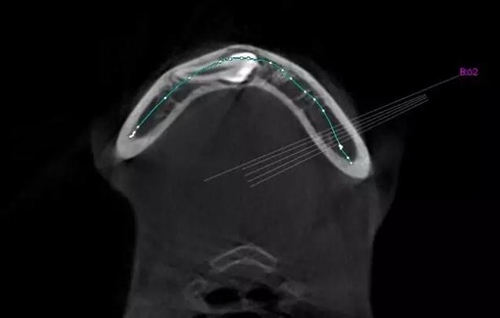

本案:患兒,女,14歲,因牙齒矯正來院,檢查見83滯留,43未見萌出,拍片發(fā)現(xiàn):43埋伏阻生于31、41、42根尖下方,按照正畸診療計(jì)劃,擬行43拔除術(shù)。

CBCT顯示